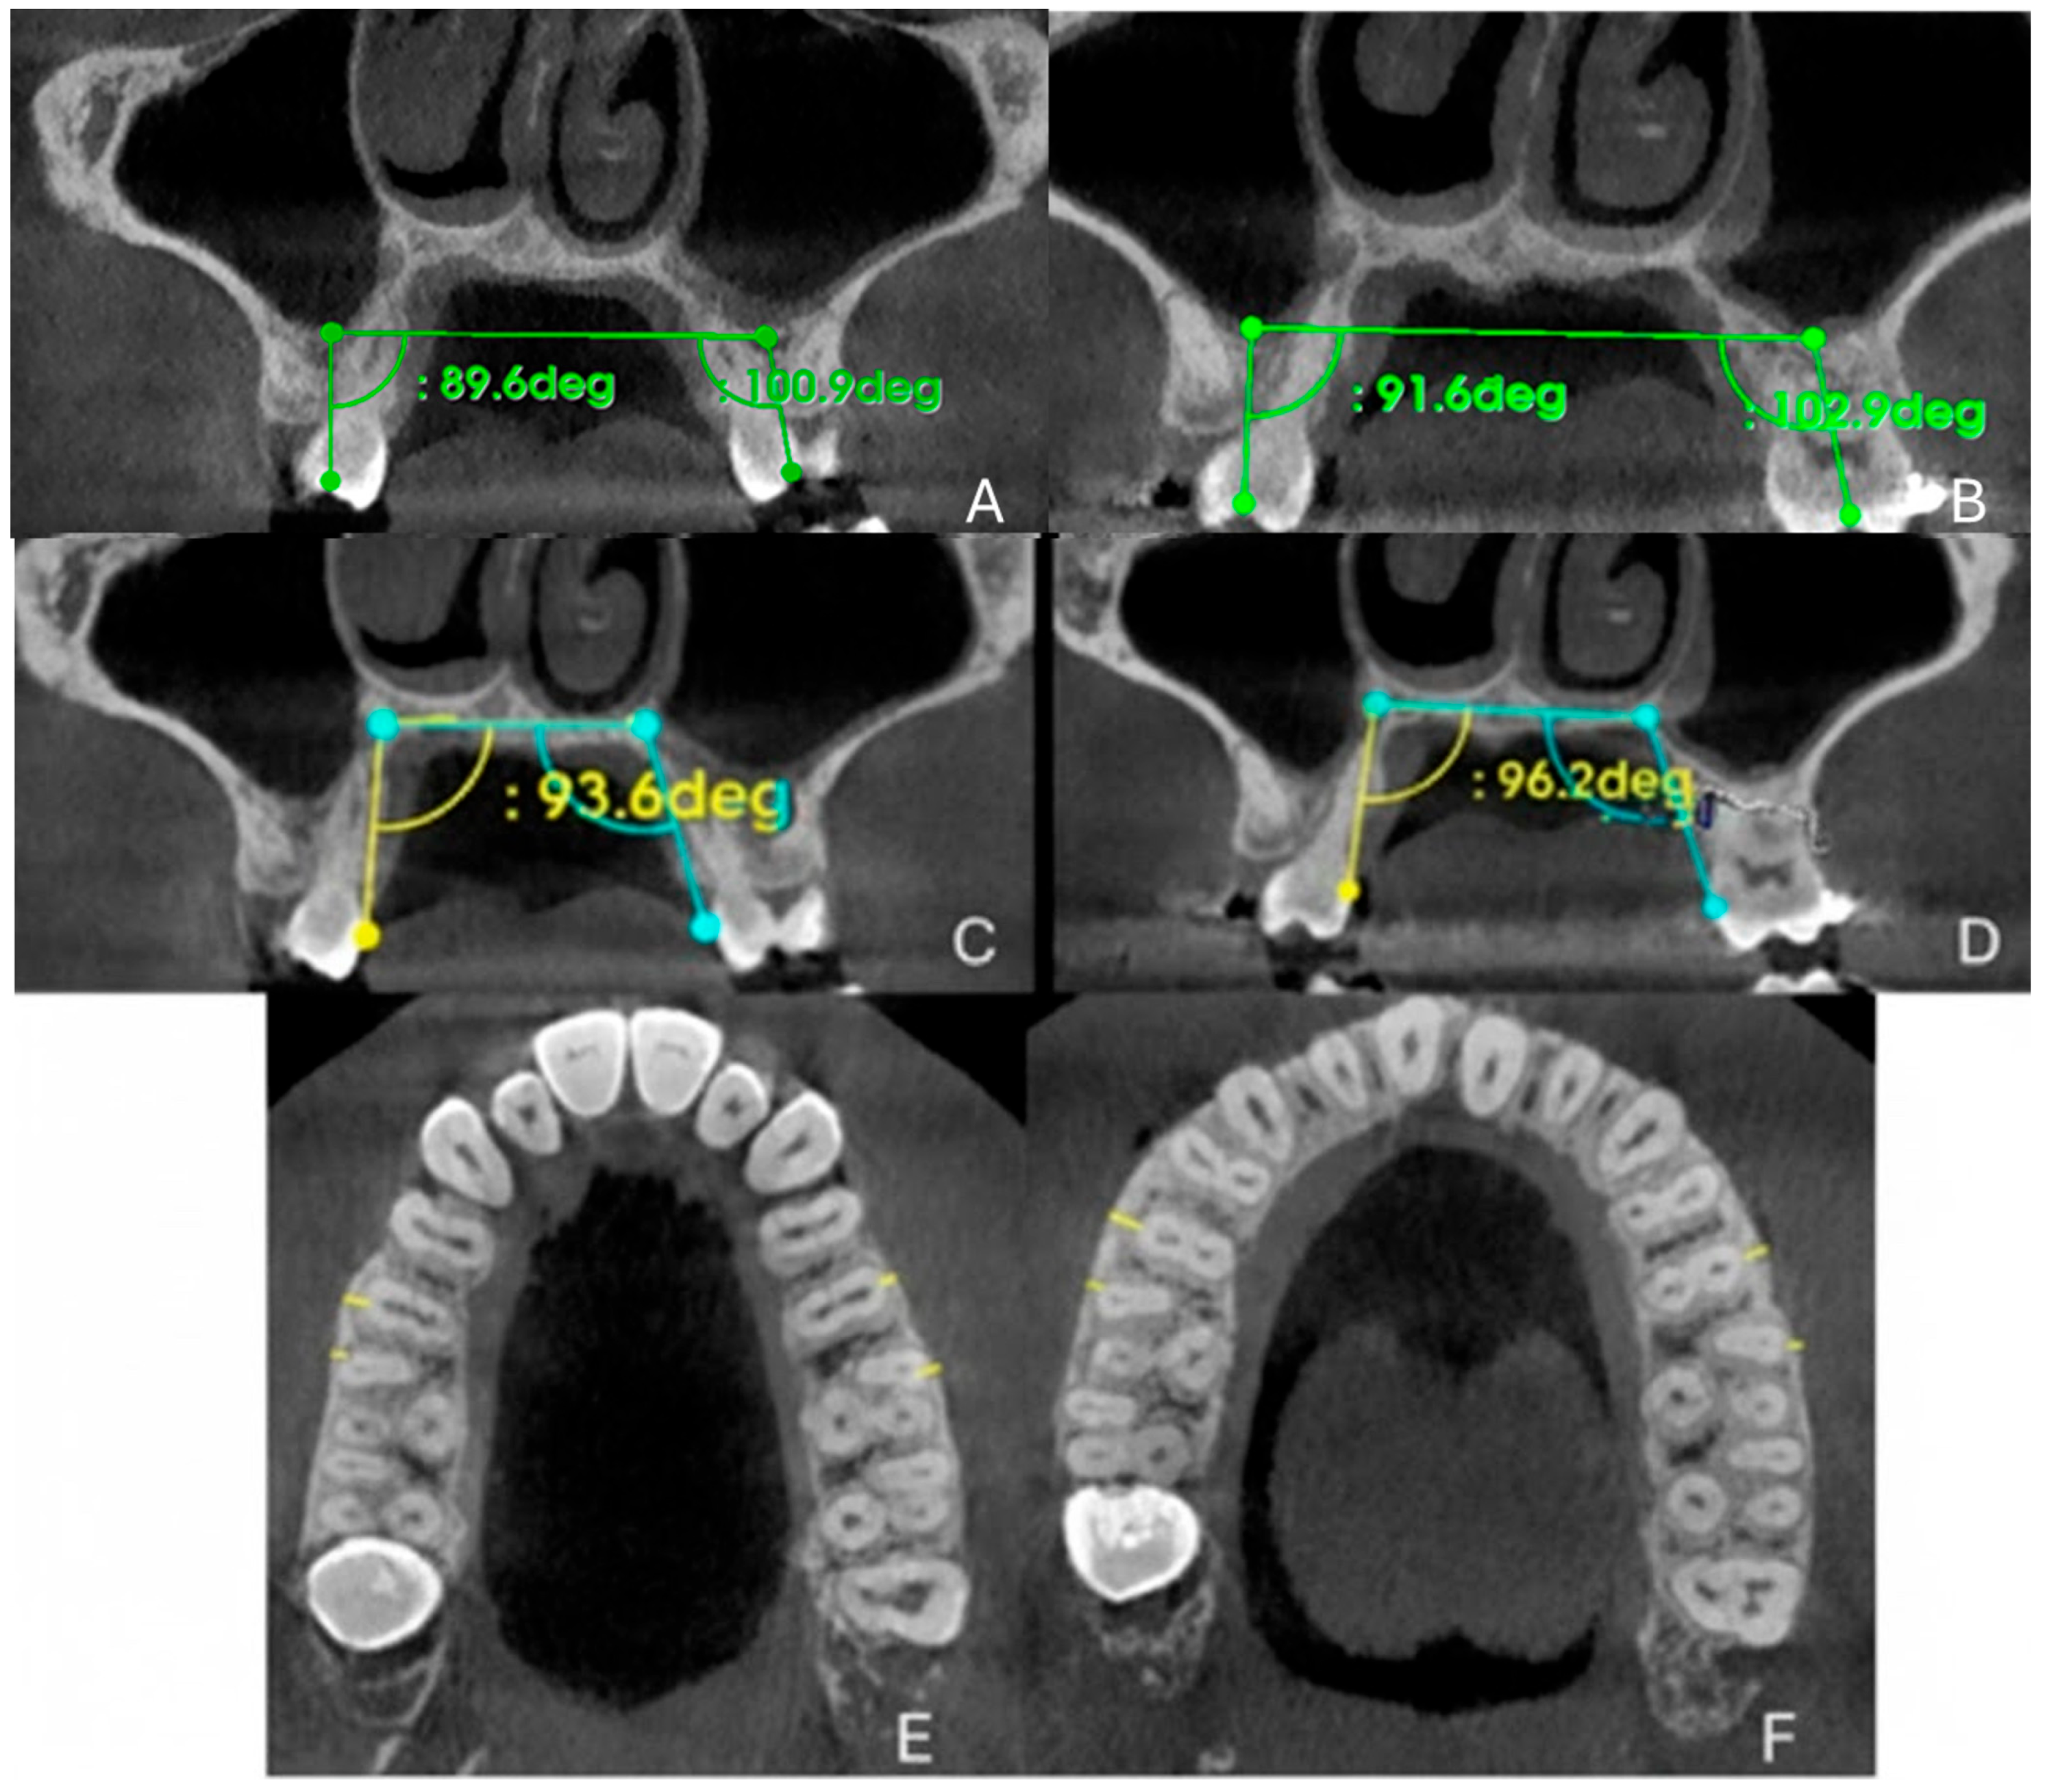

2.9.2. Quantitative Two-Dimensional Analysis of Upper Palatal Expansion on CBCT

2.9.3. Evaluation of Dental Effects: Alveolar Bending, Palatal Alveolar Angle, Dental Tipping and Bone Dehiscence

3.3. Quantitative Two-Dimensional Analysis of Upper Palatal Expansion on CBCT

3.4. Evaluation of Dental Effects: Palatal Alveolar Angle, Buccal Tipping Angle, Bone Dehiscences and Fenestrations

| Measurements | Pre-Treatment | Post-Treatment |

|---|---|---|

| PMW (mm) | 28.04 | 34.5 |

| IMW (mm) | 36.08 | 50.02 |

| SE (mm) | 0.32 | 7.82 |

| M16 (mm) | 0.6 | 0.7 |

| M15 (mm) | 1.6 | 2.3 |

| M25 (mm) | 0.7 | 1.3 |

| M26 (mm) | 1.2 | 0.9 |

| PAA 16 (°) | 93.6 | 96.2 |

| PAA 26 (°) | 109.6 | 112.2 |

| DTA 16 (°) | 89.06 | 91.6 |

| DTA 26 (°) | 100.9 | 102.9 |